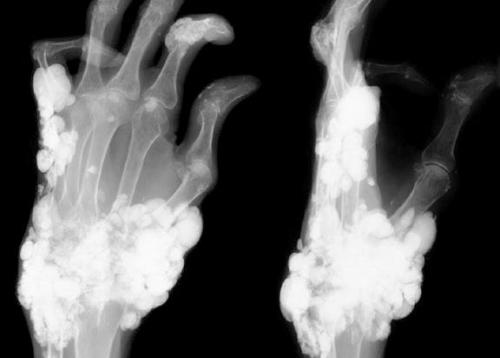

Фото: кальциноз на снимке

Фото: подагра суставов рук

Фото: тофус при подагре